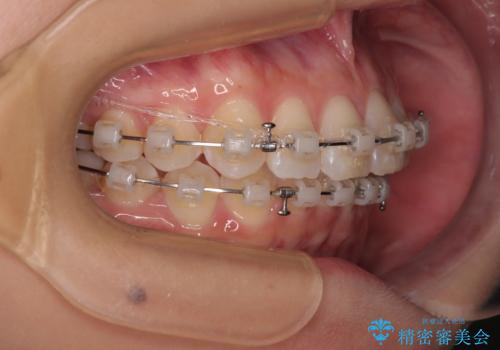

なかなか舌の突出癖が改善できず、上下前歯が非接触となる期間が長く続きました。

アンカースクリューの活用と、舌のトレーニングを何度も指導し、出っ歯になることなく無事に治療を終えることができました。